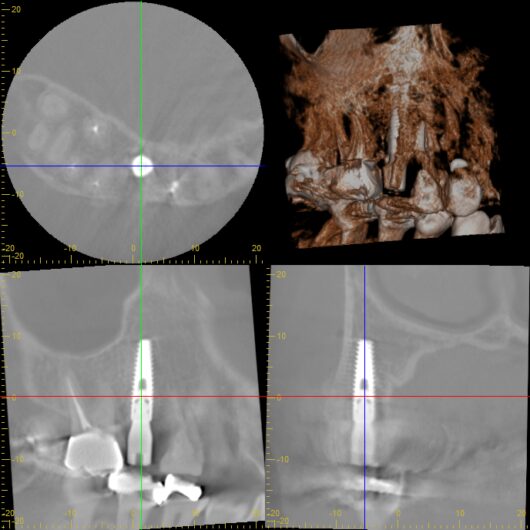

CTでシュミレーション

サージカルガイドで確実な手術を

シミュレーション結果をもとに、サージカルガイドという装置を作製しました。

これは、手術時にお口の中に装着する、いわば「インプラント埋入の設計図」のようなものです。

- 計画通りの位置・角度・深さに正確に埋入できる

- 手術時間が短縮される(患者さんの負担軽減)

- 安全性が飛躍的に向上する

- 予測可能性の高い治療が実現する

実際の手術でも、計画通りの位置にミリ単位の精度でインプラントを埋入することができました。